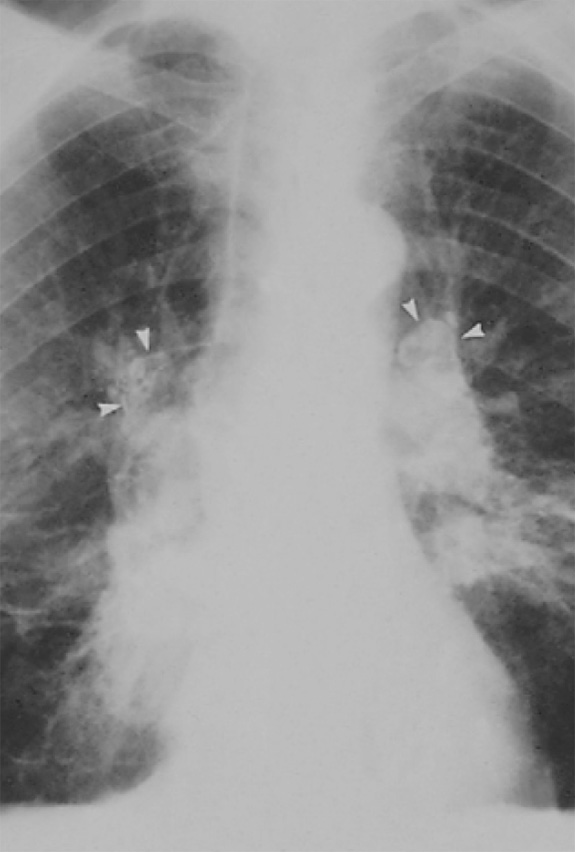

Рисунок 5. Силикоз. Определяется двусторонняя бронхопульмональная лимфаденопатия. Множество лимфатических узлов обызвествлены, в некоторых лимфоузлах отмечается обызвествление по типу «яичной скорлупы» (см стрелки)